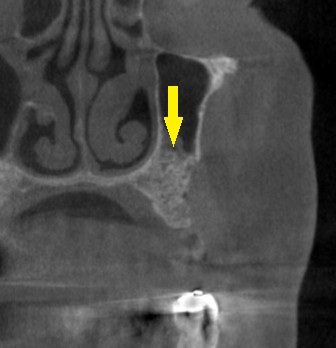

インプラント治療であれば、4歯ないところへ、2本のインプラントを埋入して、3歯回復を目指したいのですが、CTで見ると、特に2本目のインプラントを埋入したいところは、骨が非常に薄い状態でした(下の写真上段右)。

ワイドインプラントでも対応が困難と考え、サイナスリフトという骨造成をまず行って、骨量を確保することを提案させていただきました。